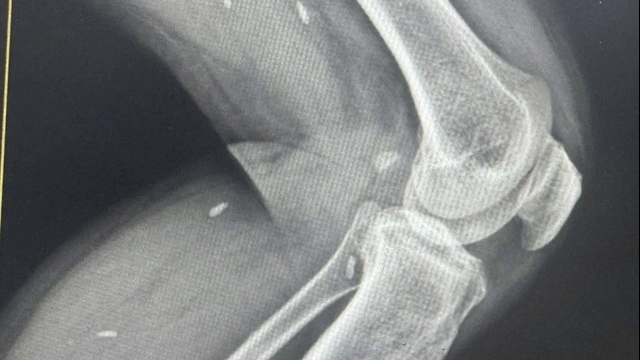

Thực hiện các kỹ thuật chẩn đoán hình ảnh như chụp X quang và CT Scan ngực, siêu âm, sàng lọc trước sinh như đối với người không mang thai, chỉ sử dụng phương tiện chẩn đoán hình ảnh này khi thật cần thiết với bức xạ liều thấp, chú ý sử dụng các phương tiện bảo vệ thai nhi.